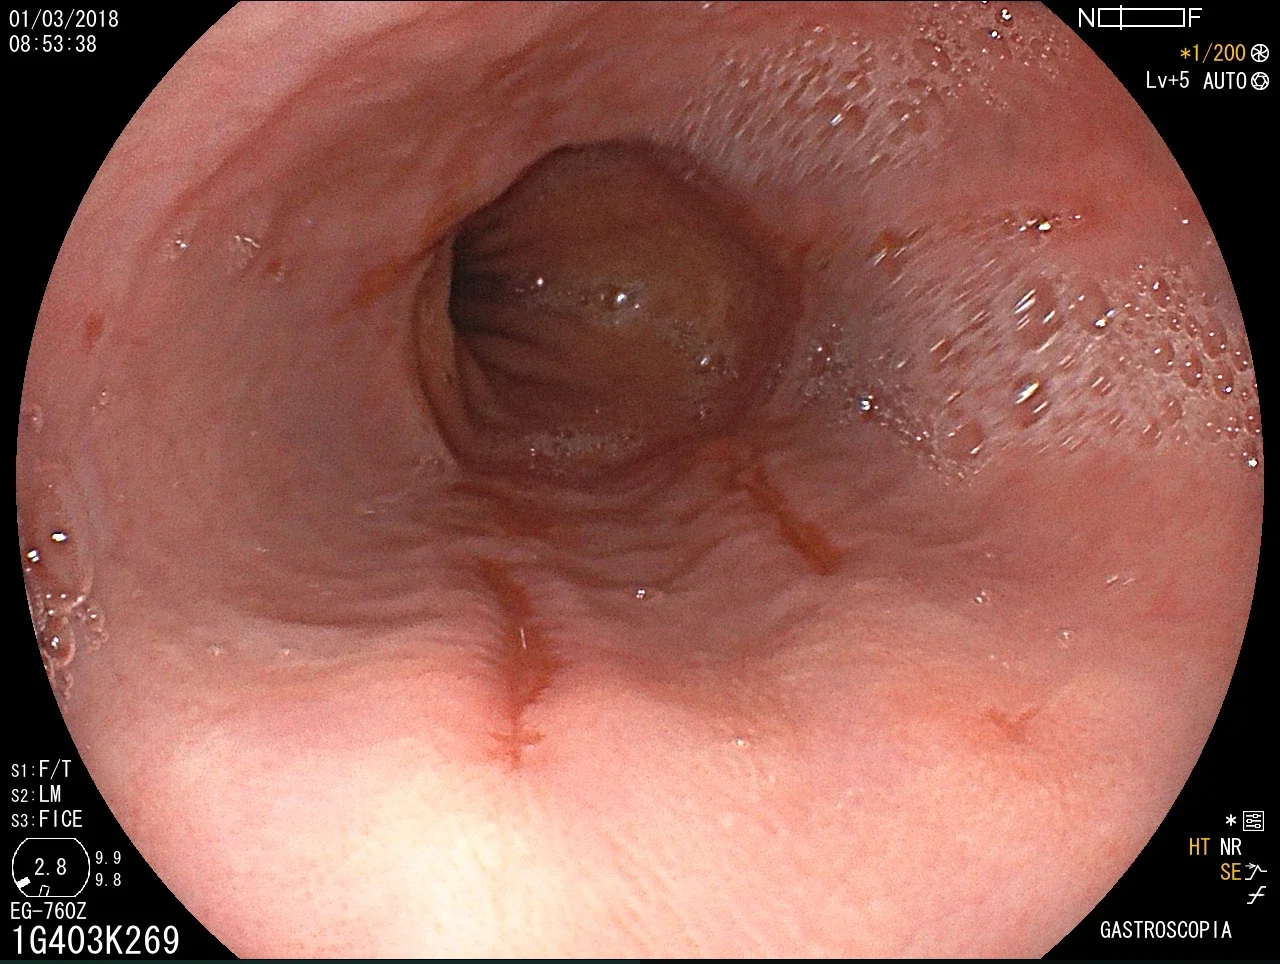

Introducción del gastroscopio bajo visión directa para examinar esófago, estómago y duodeno.

Toma de biopsias de mucosa gástrica o de lesiones encontradas.